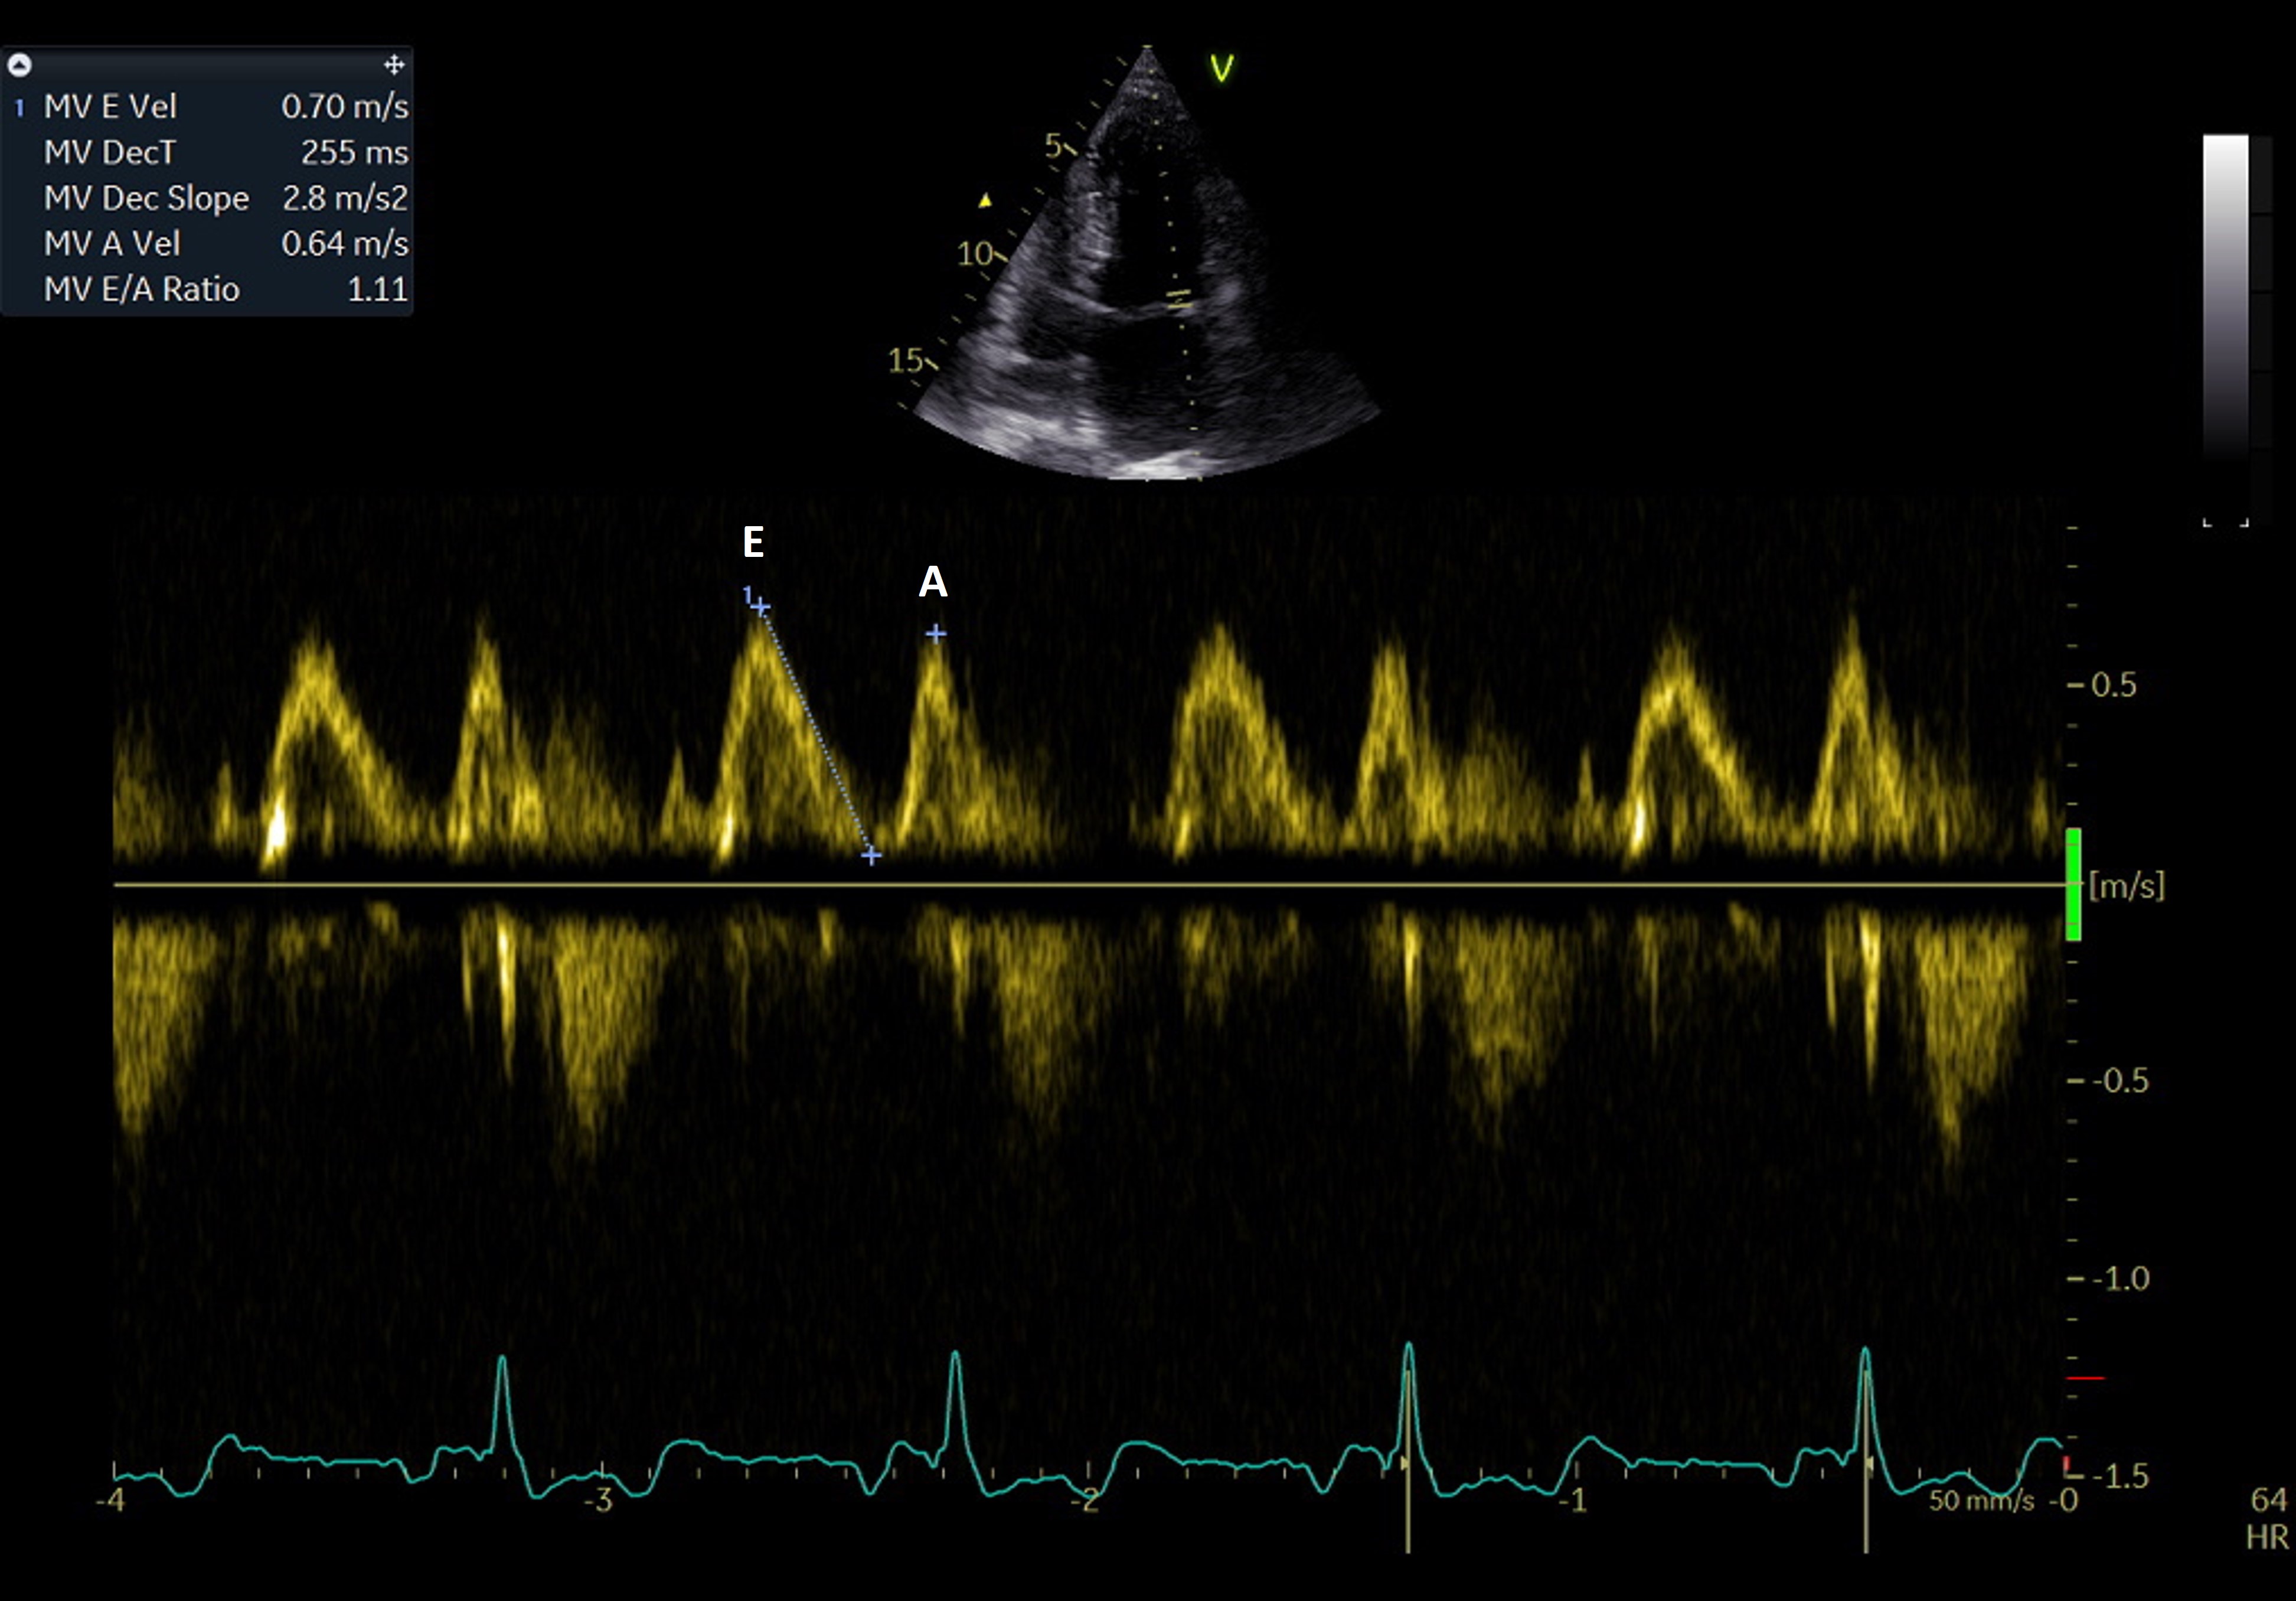

The mitral inflow pattern is evaluated using PW Doppler, with the sample volume placed at the tips of the mitral leaflets in the apical four-chamber view (Fig. 4). The evaluation demonstrates the passive LA filling during ventricular diastole (the E wave) and the active late filling due to atrial contraction (the A wave). The E/A ratio in healthy, euvolemic young adults is typically higher than 1. The ratio depends on age and the E wave decreases in older individuals, resulting in a ratio below one.

Fig. 4.

Fig. 4.PW Doppler evaluation of the transmitral diastolic flow. E wave – early diastolic filling of the LA; A wave – late diastolic filling determined by atrial contraction.

In patients with AF, beat-to-beat variability and absence of the A wave make the E/A ratio impossible to assess. Moreover, the hallmark of LA dysfunction is the loss of atrial contraction in AF: the A wave disappears, but restoration of SR results in its reappearance. The loss of atrial contraction, which accounts for up to 30% of left ventricle filling, will determine a reduced ventricular volume, while creating a volume overload for the LA. This results in progressive LA dilation, determining myocyte disarray and fibrosis. The A wave velocity is evaluated as a surrogate of LA contraction function, as full recovery of mechanical activity does not occur immediately after successful SR restoration. Thus, A wave velocity after cardioversion to SR from AF is low, as far as LA systolic function does not promptly recover. This phenomenon is described as “LA stunning”. Left atrium stunning may persist between 24 hours for the paroxysmal pattern [62] and up to 3 weeks [63] after cardioversion, depending on the duration of AF [64].

A higher than 2 E/A ratio in patients with SR indicates a restrictive pattern of LV diastolic function. This is associated with an E wave deceleration time lower than 140–160 msec and an IVRT lower than 50 msec. This pattern is indicative of increased LV end-diastolic pressure, and it predicts high LA pressure and volume. A restrictive diastolic mitral flow pattern is correlated with mortality in patients with heart failure [65]. A high E/A ratio that results from restrictive LV conditions should not be confused with that observed after AF cardioversion when A wave velocity is low due to atrial stunning.